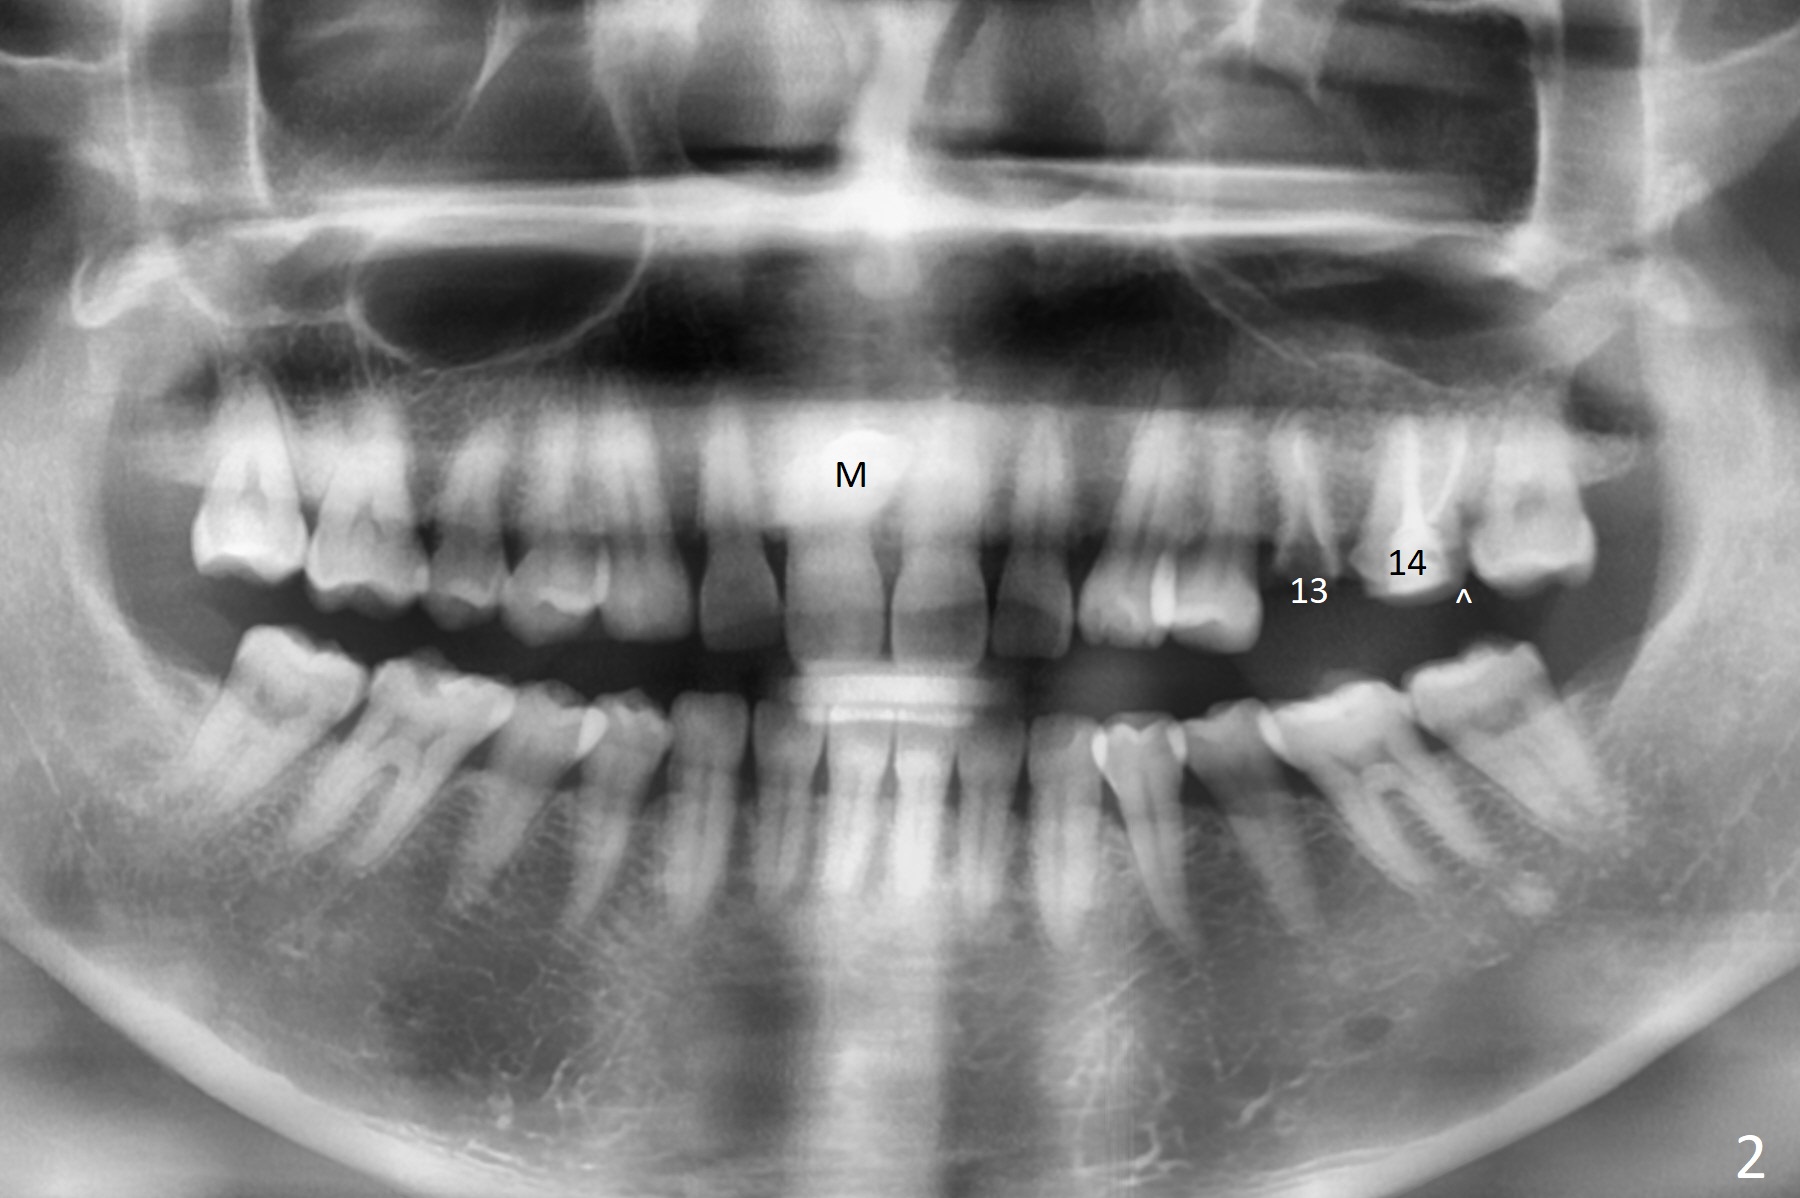

A 44-year-old woman used to have splinted crowns at #13 and 14 (Fig.1). Their dislodgement is due to residual roots at #13 and distal caries at #14 (Fig.2 ^). To avoid the distally curved apex of #12 and to have ideal trajectory of an IBS implant (Fig.4), osteotomy will be initiated in the distopalatal slope of the socket (Fig.3 arrowheads). The patient wants to correct the tooth #8 with rotation (Fig.5), which is due to a mesiodens (Fig.1,2 M). It will be accessed palatal (Fig.5 P). In fact there is percussion at #14 associated with MB2 (Fig.6 arrowheads) and PARL (*).